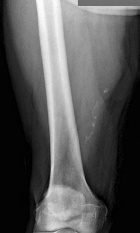

77 year old male c/o right thigh mass

Zoom image: Radiological image Radiological image.